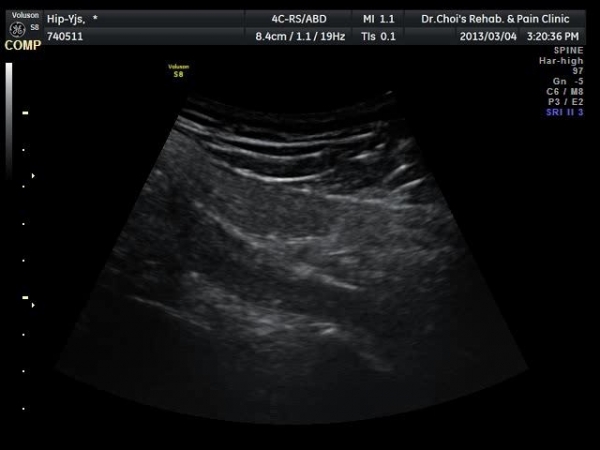

[¾ûµ¢ÀÌ] pirifrormis ±ÙÀ° ÁÖ»çÄ¡·á

ÃÊÀ½ÆÄ °Ë»ç